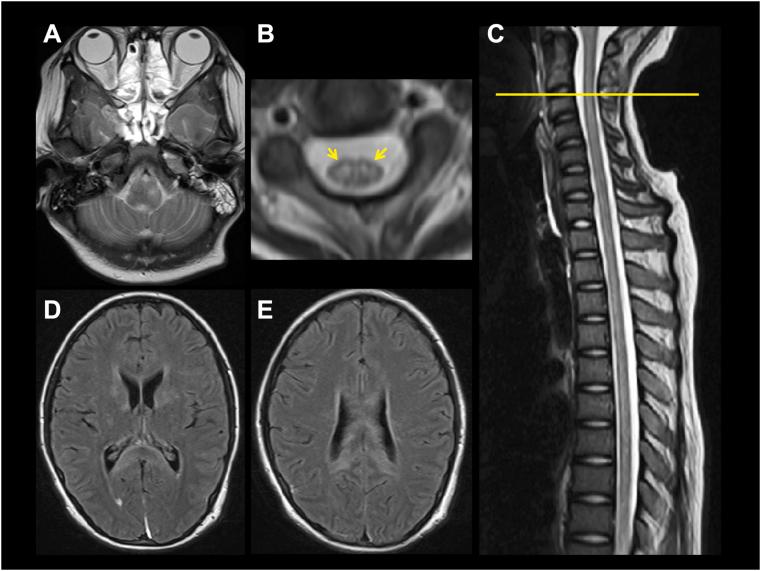

一名12岁女孩出现脑膜炎症状。随后她出现意识障碍和弛缓性四肢瘫,因呼吸衰竭接受机械通气。MRI显示脑白质、基底神经节、延髓以及C2至Th1和Th11至L1水平脊髓前角有病变。神经传导研究显示运动神经轴索性神经病。经过类固醇冲击治疗(激素冲击疗法)、大剂量免疫球蛋白治疗和血浆置换后,病变逐渐消退,神经症状稳步改善。发病6个月时神经后遗症极少。尽管血清抗水通道蛋白4和抗髓鞘少突胶质细胞糖蛋白抗体均为阴性,但她的血清和脑脊液中抗乳糖酰鞘氨醇抗体呈阳性,表明这些抗体可能参与了该疾病的发病机制。